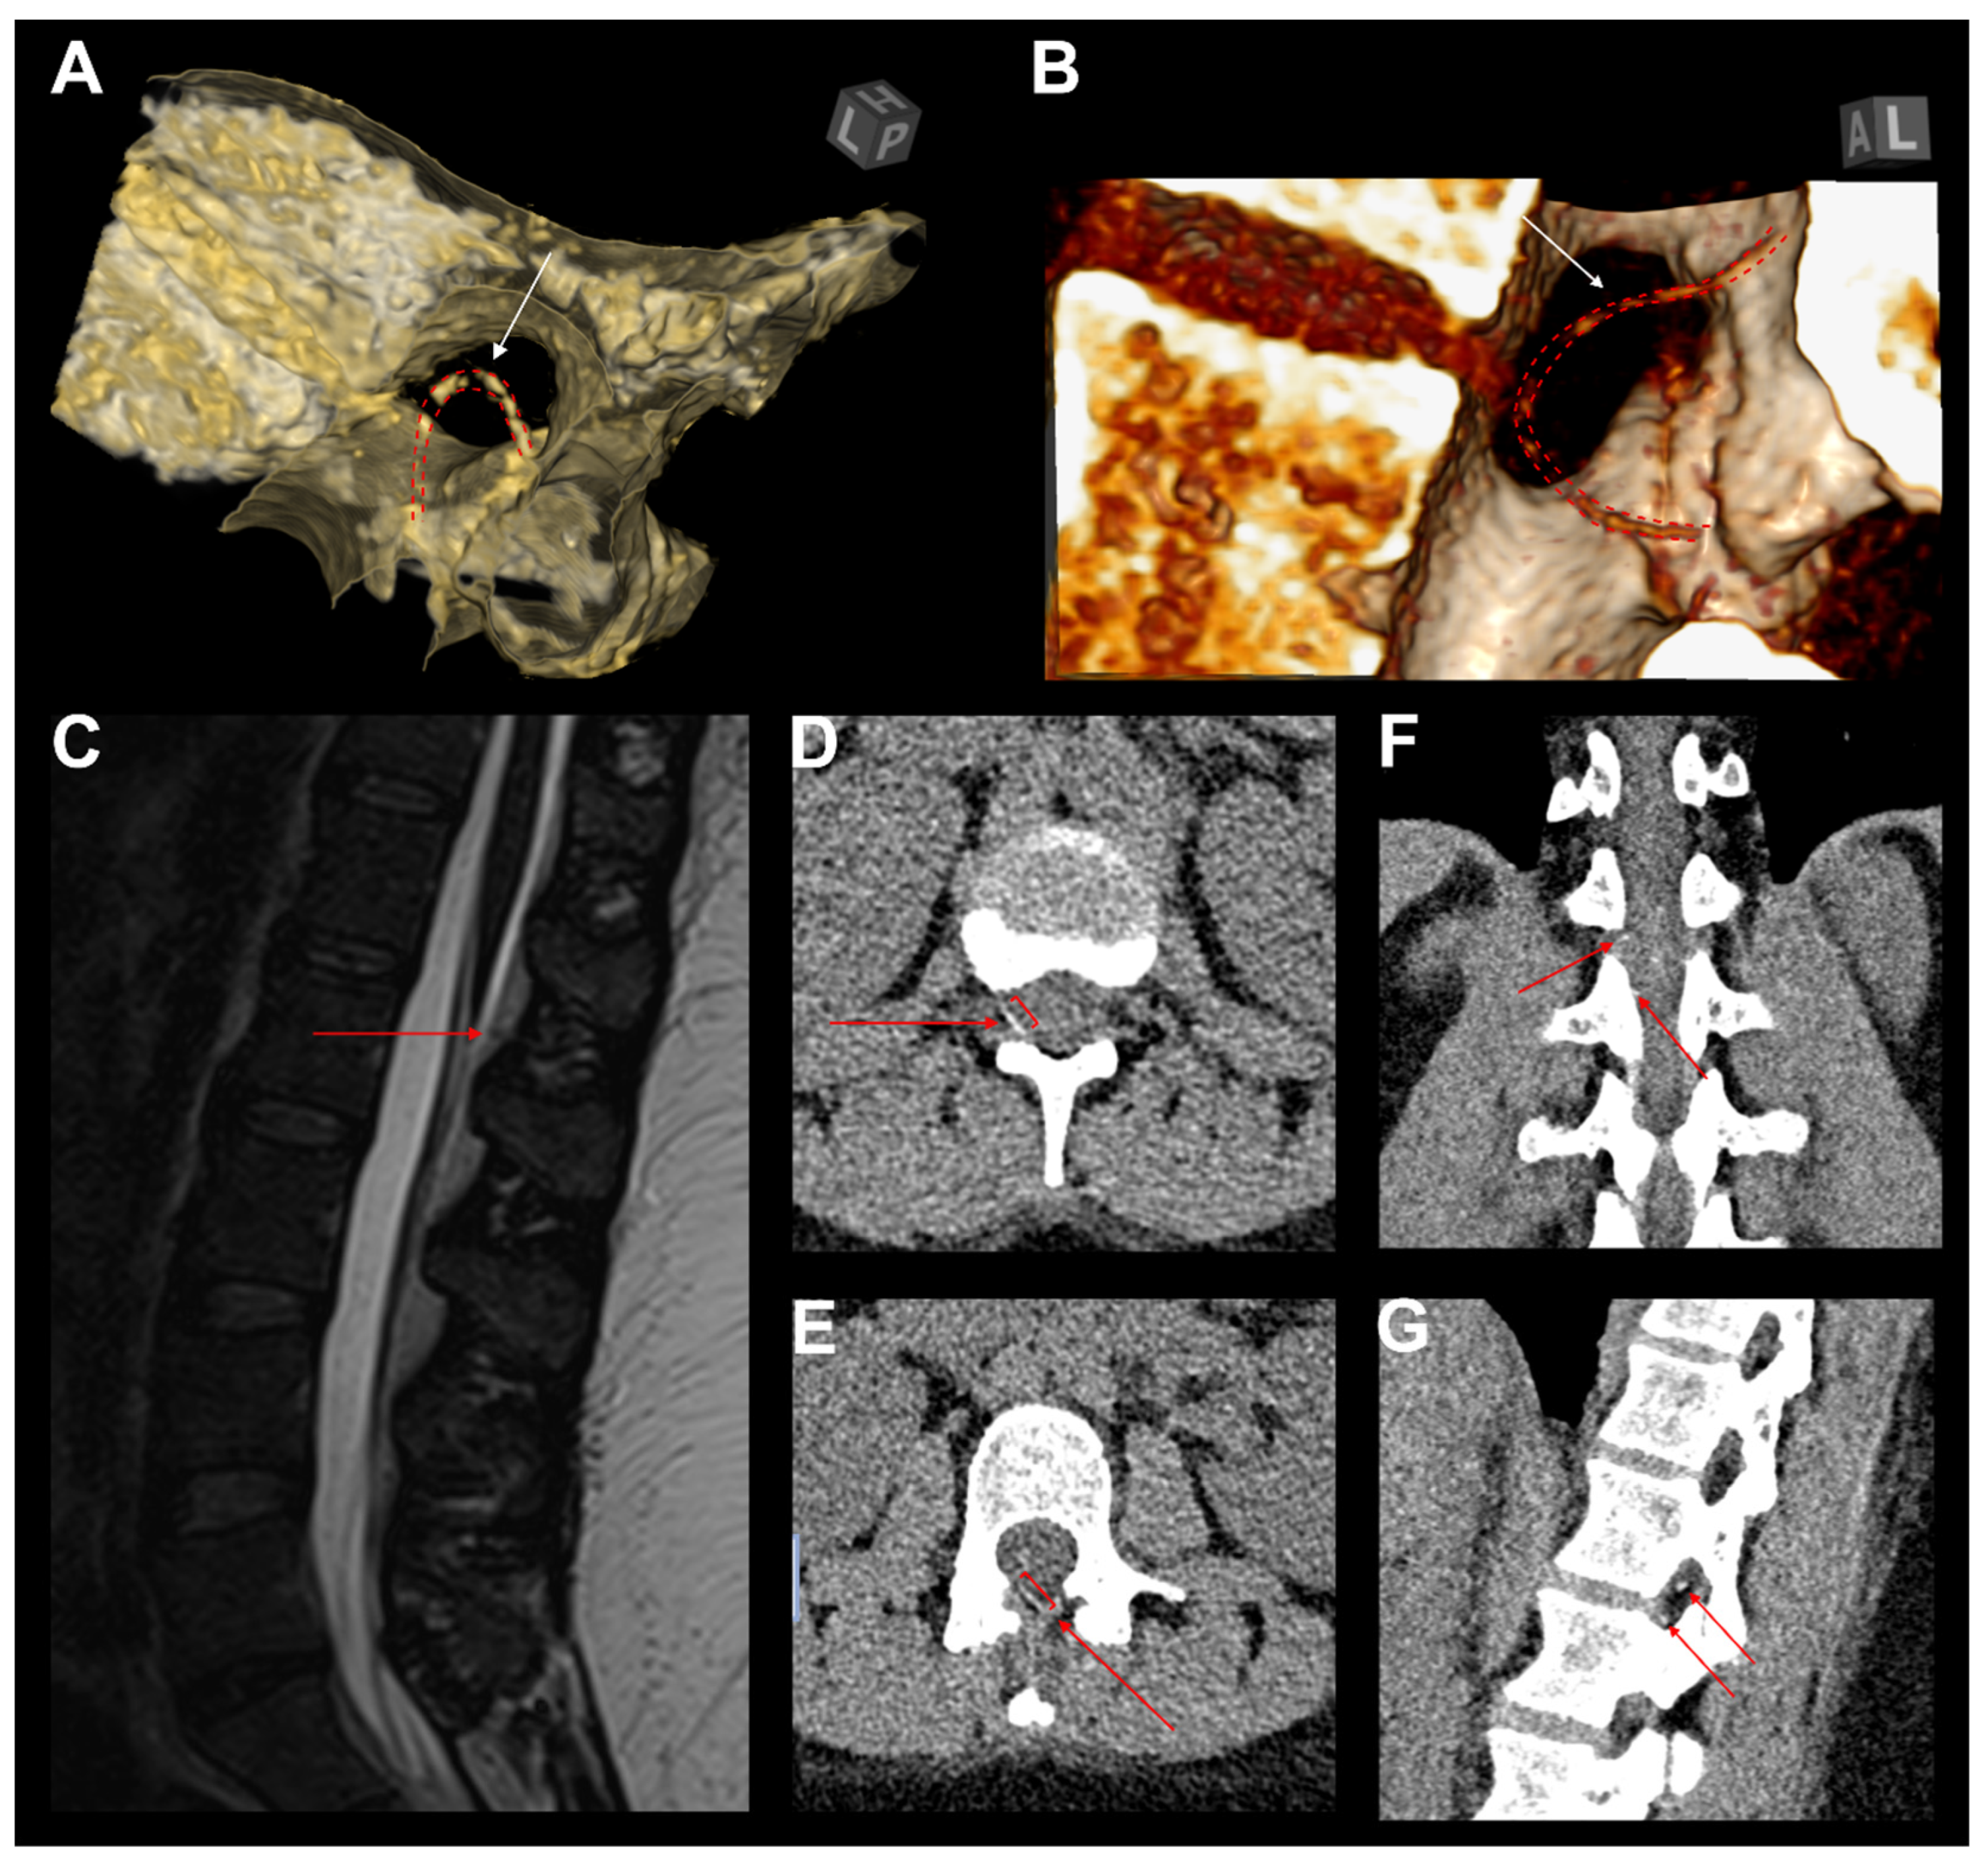

3.8. Illustrative Case